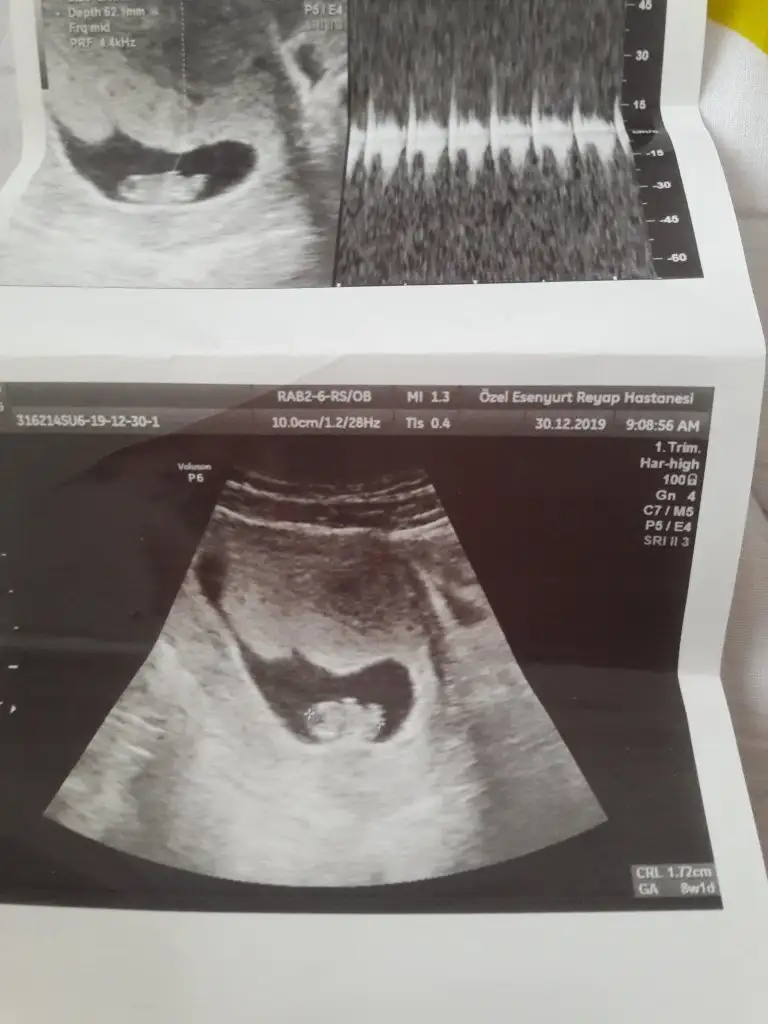

MaşAllah canımEki Görüntüle 2570165 bugün kontrolum vardı kizlar

Eki Görüntüle 2570165 bugün kontrolum vardı kizlar

Benim rahim ters vajinal baktı ve bebegide gördük ben 5+3um bugun